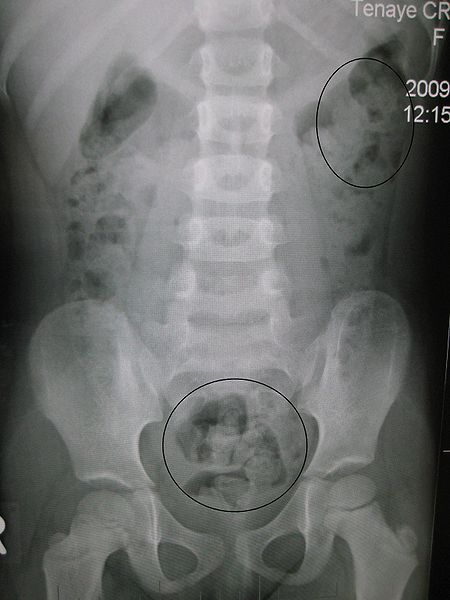

Каловый камень представляет собой конкремент, образующийся в кишечнике из-за нарушения пищеварения и недостатка жидкости. Врачи отмечают, что симптомы, такие как боли в животе, запоры и чувство тяжести, могут указывать на наличие этого образования. Диагностика включает в себя рентгенографию, ультразвуковое исследование и колоноскопию, что позволяет точно определить размер и местоположение камней.

Для диагностики незначительных камневых новообразований требуется проведение следующих видов исследований:

- колоноскопия;

- эхография;

- рентгенографическое;

- ультразвуковое;

- компьютерная томография брюшной полости.

Такая комплексная диагностика дает специалисту возможность не только поставить точный окончательный диагноз, но еще и опередить размеры каловых камней, их точную локализацию. На основании полученных результатов пациенту назначается оптимальное, наиболее эффективное для конкретной клинической ситуации лечение!